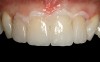

Fig 19. Preparations and abutment after provisionals removed.

Figure 19

Clinical Procedure Phase 3

The provisionals were removed, and tissue health was evaluated (Figure 19). The crowns were tried in and marginal integrity and proximal contacts verified. A water-soluble veneer cement try-in gel was used to evaluate shade and overall esthetics. After patient approval, the crowns were removed and the internal aspect was cleaned with 35% phosphoric acid, rinsed, and air-dried thoroughly. A silane coupling agent was placed on the intaglio surface and allowed to remain for 60 seconds and air-dried. An unfilled, HEMA-free resin was applied as a very thin layer on this surface and then air-thinned but not light-polymerized. The crowns were then filled using a light-cure-only resin cement and set aside in a light-protective container.